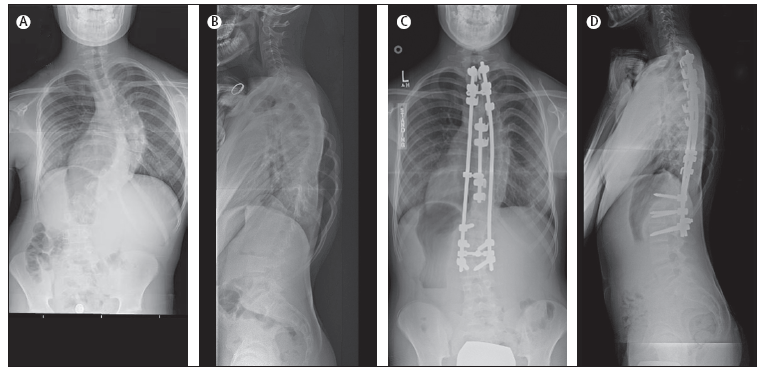

A. Radiografia

posteriore-anteriore preoperatoria; B. Radiografia laterale

preoperatoria; C. Radiografia posteriore-anteriore postoperatoria; D.

Radiografia laterale postoperatoria.

Gli

interventi sono in generale attuati per via posteriore (Figura

3 e Figura 4). La via anteriore viene